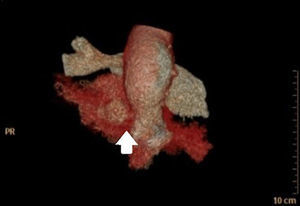

Sixty-six year-old patient with a mechanical aortic prosthesis implanted two months ago, who recently experienced a deterioration in his level of consciousness and a sudden-onset fever of up to 39°C, along with a bluish nodular lesion in the fifth digit (little finger) of his left hand. The brain CAT scan performed revealed a parietal intraparenchymal hemorrhage, of which blood cultures were taken (with a positive result for Staphylococcus aureus). Furthermore, the transthoracic echocardiogram (TTE) carried out showed a poorly differentiated hyperechogenic image at the level of the prosthetic valve. Based on the above findings, a transesophageal echocardiography (TEE) was also performed revealing the presence of a metallic aortic valve prosthesis associated with periaortic thickening (arrow, Fig. 1) along with images of cavitated lesions in the posterior end of the aortic root (asterisk, Fig. 2), one of which was seen to come into contact with it, thus being suggestive of a complicated endocarditis. Additionally, a cardiac CAT scan showed a 9-mm heart wall defect coming into contact with a 9×6×5.5-cm collection, as well as contrast media extravasation suggestive of a broken pseudoaneurysm contained by the epicardium (arrow, Fig. 3). This case report brings to light the key role of TEE in detecting cases of endocarditis.